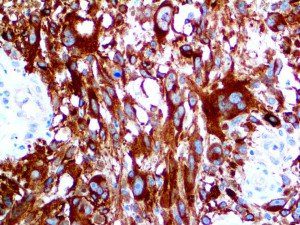

It is the ICU physician who is most likely to witness one of the deadliest manifestations of the abnormal immunological response, the cytokine storm syndrome (CSS). This response is also referred to by some as the cytokine release syndrome (CRS). CSS is characterized by continuous activation and expansion of macrophage and lymphocyte populations, which secrete large amounts of cytokines, causing the cytokine storm. This massive cytokine release is akin to hemophagocytic lymphohistiocytosis (HLH) disease, a syndrome characterized by initial unchecked and persistent activation of cytotoxic T lymphocytes and NK cells.

Clinical and laboratory manifestations of HLH include fever, enlarged liver and/or spleen, neurologic dysfunction, coagulopathy, liver dysfunction, cytopenias (i.e., low levels of erythrocytes, leukocytes, and/or platelets), hypertriglyceridemia, hyperferritinemia, hemophagocytosis, and eventually diminished NK cell activity as the immune system becomes progressively paralyzed. HLH can be familial (primary HLH) or secondary to another disease process (sHLH), such as rheumatic disease, in which it is referred to as macrophage activation syndrome (MAS, characterized by elevated ferritin).